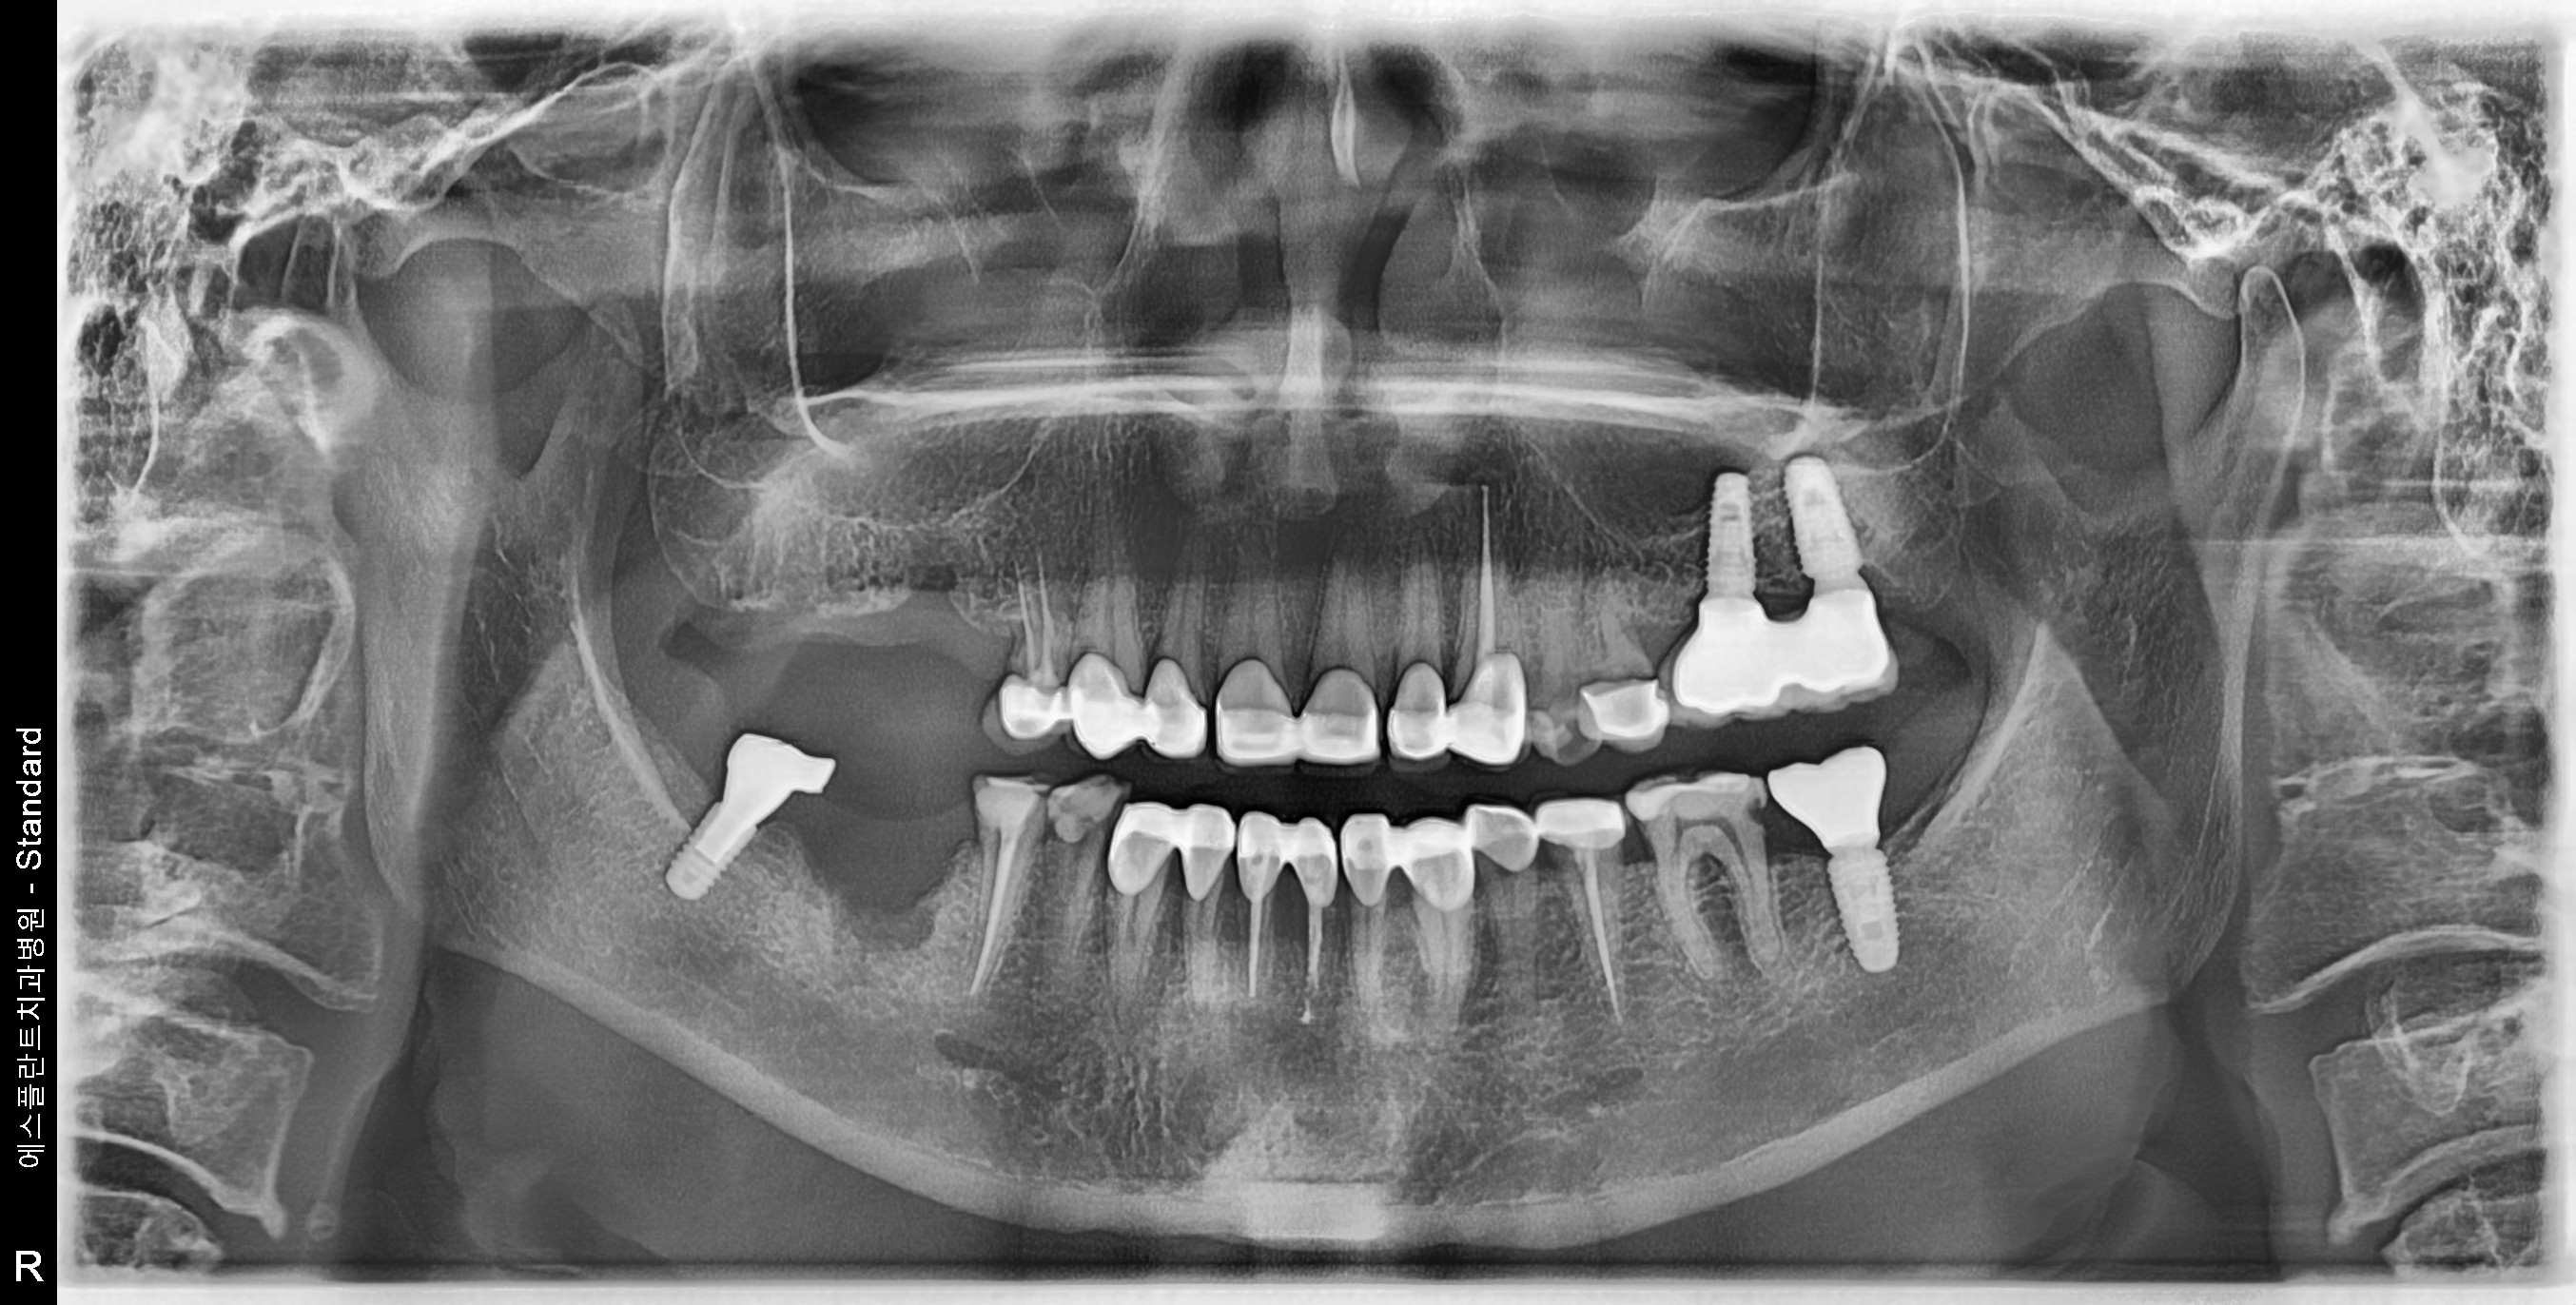

Esthetic prosthetic remake, Dental Implant, Sinus-lifting, Bone Graft

59 y.o, Kazakhstan, Astana

Operating dentist:Roh Hyun Ki